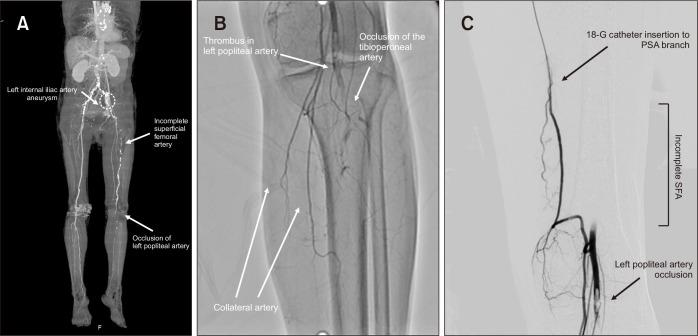

Persistent sciatic artery (PSA) is a rare congenital peripheral artery disorder that is usually detected incidentally on computed tomographic examination. PSA can also cause iliac aneurysm and acute thromboembolism, which are potentially associated with rest pain, claudication, and limb-threatening ischemia. Patients with PSA and leg ischemia should be treated with revascularization and appropriate management of PSA aneurysm. The authors often choose emergent bypass surgery or endovascular intervention for aneurysmal rupture and acute lower-extremity arterial occlusion. This report describes an emergency procedure using catheter-based thrombolysis for acute limb ischemia in a patient with PSA.

持续性坐骨动脉(PSA)是一种罕见的先天性外周动脉疾病,通常在计算机断层扫描检查中偶然发现。PSA还可导致髂动脉瘤和急性血栓栓塞,这可能与静息痛、间歇性跛行以及威胁肢体的缺血有关。患有PSA和腿部缺血的患者应接受血管重建术并对PSA动脉瘤进行适当处理。对于动脉瘤破裂和急性下肢动脉闭塞,作者通常会选择紧急搭桥手术或血管内介入治疗。本报告描述了一例使用基于导管的溶栓术治疗PSA患者急性肢体缺血的急诊手术。